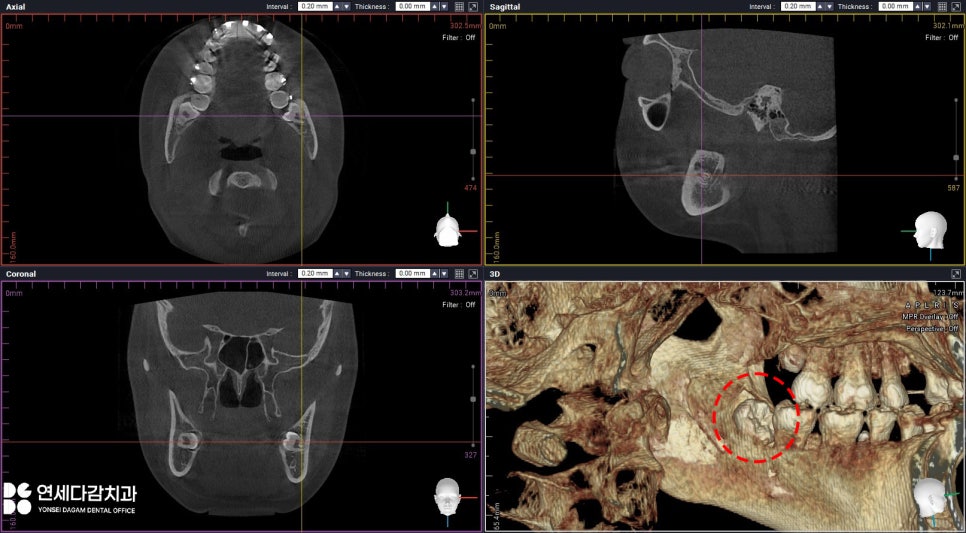

매복되어 있는 경우 잇몸과

턱뼈 깊숙이 위치하고 있는

경우가 많기 때문에,

단순한 파노라마 사진만으로는

주변 신경 구조물과의

관계를 명확히 파악하기 어렵습니다.

따라서 CT를 통해 3차원적으로

해부학적 구조물을 정밀하게

분석해야 됩니다.

끝 쪽에 위치하는 치아는

여러 구조물과 겹치거나

밀접한 경우가 많기 때문에,

불필요한 졸개 및 조직 손상을

방지하기 위한 필수 과정이죠.

오금동 치과 에서는 우선 아래 치아부터

진행하기 위해 오른쪽을

먼저 살펴봤습니다.

매복되어 있긴 했으나

조심해야 될 구조물들과

가까운 편도 아니었고,

안정적으로 나올 수 있을 것으로

판단됩니다.

이렇게 큰 어려움 없이

뺄 수 있었으나,

중요한 것은 왼쪽 아래였는데요.

CT를 살펴보면 교합면(치아의 윗면)이

설측으로 수평 매복된 형태였습니다.

설측 점막에는 특히

신경과 혈관이 밀접해 있기 때문에

절개 및 박리 시 주의해야 됩니다.

무리한 접근 시 감각 저하 등의

부작용이 생길 수 있기 때문입니다.